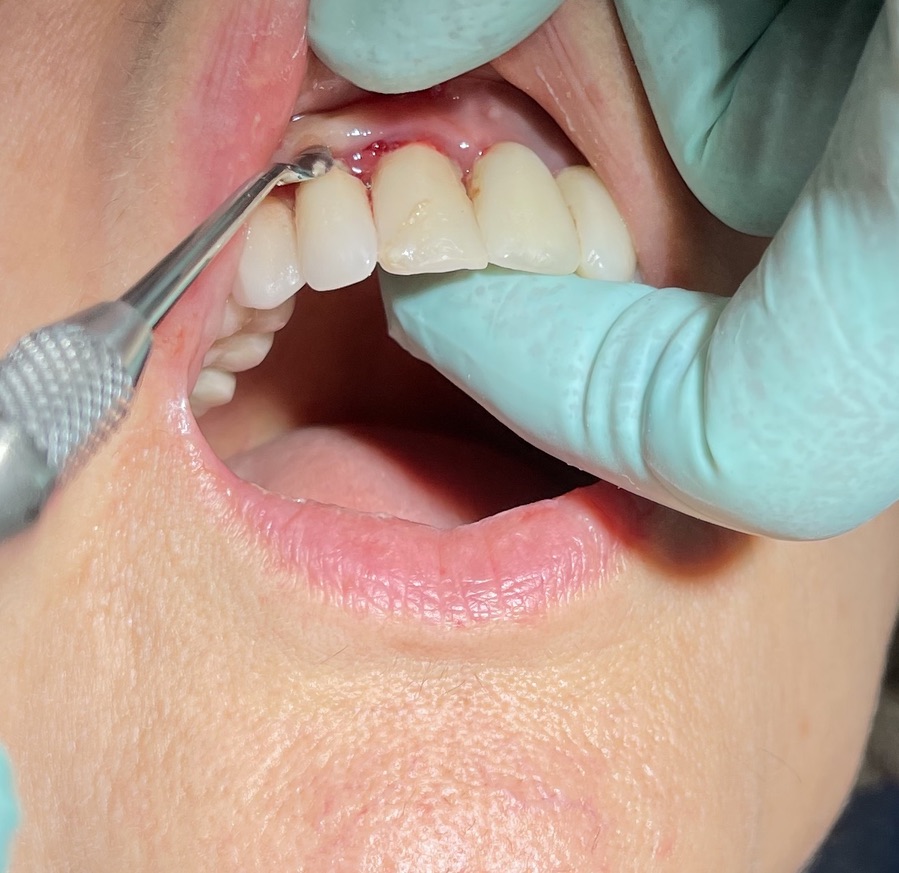

Spessore della mucosa spessa media sottil: media

Descrizione intervento

Complicanze: assenti